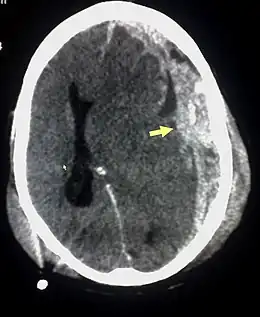

Le diagnostic se fait au scanner sans injection. Son accès est facile dans les pays développés. Il n'existe pas de contre-indication (sauf la grossesse).

Sur le scanner crânien, fait sans injection de produit de contraste, l'hématome sous-dural se présente habituellement sous une forme de croissant, dont la concavité suit la courbe du cerveau, stoppé seulement par les réflexions durales telles que la faux du cerveau et le tentorium. Cependant ils peuvent avoir une forme convexe, spécialement tout au début du saignement, ce qui peut les faire confondre avec les hémorragies épidurales (hématome extradural). Le sang peut être vu comme une densité stratifiée tout au long du tentorium. Dans les cas chroniques, on peut voir l'effacement des sillons ou le déplacement médian de la jonction substance blanche/substance grise, mais le sang peut avoir une densité très proche de celle du tissu cérébral (isodense), ce qui peut masquer l'hématome.